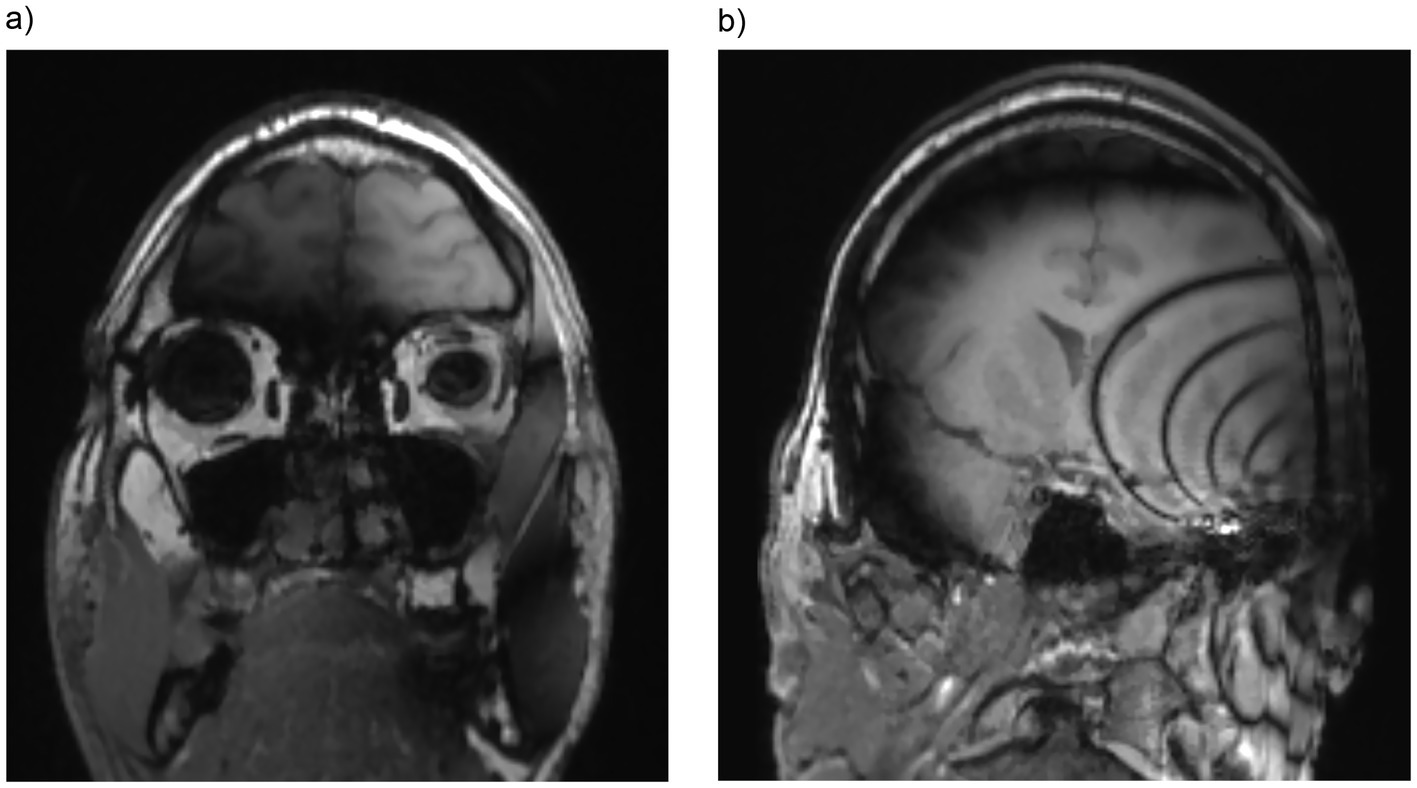

The evaluation of the paranasal sinuses was conducted as follows: the maxillary, frontal, and ethmoid sinuses were assessed separately for each side. The ethmoidal cells were evaluated as a single unit, while the sphenoid sinus was considered a single unit, as an intersphenoid septum is not always present anatomically. As demonstrated in Table 2 and Figure 3, the included sequences allowed for a clear diagnostic evaluation of the maxillary and frontal sinuses, as well as the ethmoidal cells, except for DWI. The nasal cavity was also clearly visible in T1 and T2 sequences and unaffected by artifacts. However, the sphenoid sinus was partially obscured by artifacts, particularly in bilateral CI condition. After magnet explantation, the sphenoid sinus became assessable even in bilateral CI cases.

Figure 3

Both maxillary sinuses are fully visible and assessable in T1-weighted sequence (a) in a unilateral CI with a magnet positioned at a 90° angle. Furthermore, T1-weighted sequence (b) in a unilateral CI with a magnet positioned at a 120° angle demonstrating that the sphenoid sinus is only partially assessable. Coronal images are reconstructed from the volumetric T1 MP-RAGE sequence.

The clivus, an anatomical structure in the central skull base, was evaluated separately (Table 2), as it can be affected by space-occupying lesions in the sphenoid sinus (15) and by large nasopharyngeal tumors. This structure was only assessable, particularly in bilateral CI condition or at oblique angles ipsilaterally, after magnet explantation. DWI was only assessable as category 2 for unilateral 135° condition for the contralateral frontal sinus. Except for this, all other DWI images of the paranasal sinuses were not assessable due to the artifacts (category 3 and 4—see Table 2).